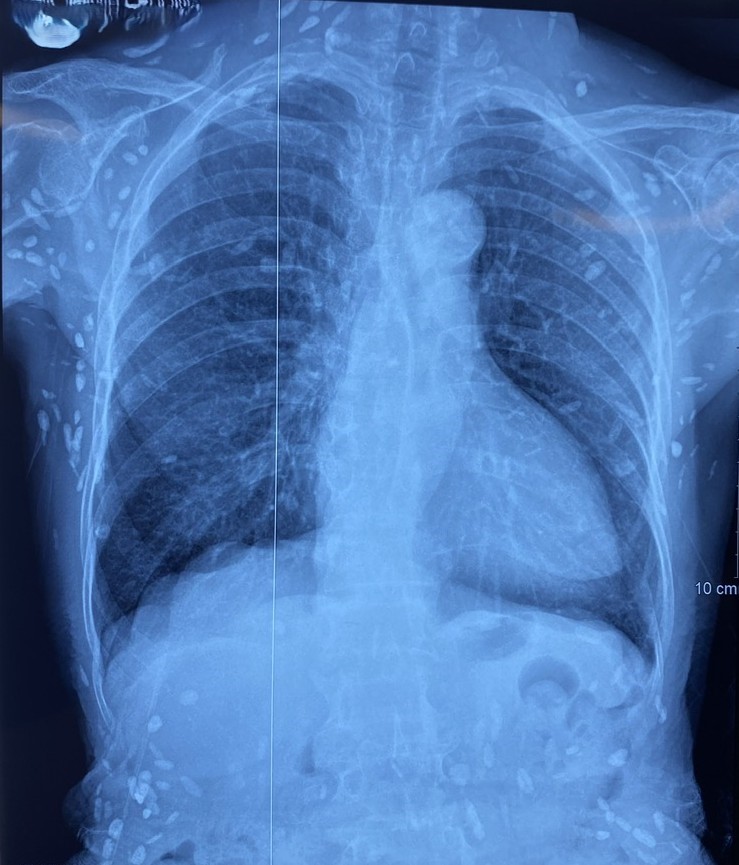

Nhiều nốt cản quang dưới da thành ngực-bụng và chi trên. Ảnh: Bệnh viện TWQĐ 108

Mặc dù xét nghiệm kháng thể IgM với sán dây lợn âm tính, các tổn thương trên X-quang gợi ý người bệnh trước đây bị nhiễm ấu trùng sán dây lợn, sau đó các nang sán trở nên vôi hóa và tồn tại lâu dài trong tổ chức. Người bệnh được điều trị theo phác đồ bệnh chính, đáp ứng và ra viện tiếp tục điều trị theo tuyến.

Nang sán dây lợn có thể tự thoái hóa hoặc bị vôi hóa, tạo nên nhiều hình ảnh cản quang phát hiện được trên phim X-quang như trường hợp bệnh nhân trên.